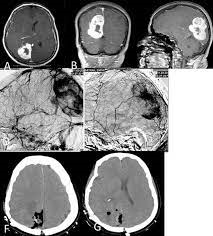

Менингеальные HPC (MHPC) составляют от 2% до 4% менингеальных опухолей и менее 1% всех внутричерепных опухолей. Внутричерепные менингеальные геменгиоперицитомы (MHPC) могут иметь общие черты с менингиомами с точки зрения клинических, гистопатологических и иммуногистохимических признаков, что вызывает трудности в дифференциальной диагностике. Однако, хотя менингиомы редко метастазируют, MHPC метастазируют значительно чаще, в то время как для общих HPC сообщается о 48% местных рецидивов и 6% метастазов; Имеются публикации, сообщающие о экстракраниальных метастазах от 25% до 60% для MHPC. MHPC могут быть более метастатическими, чем HPC, наблюдаемые в других частях тела; однако при обзоре общей литературы мы думаем, что этот показатель не достигает 60%. Всемирная организация здравоохранения классифицирует MHPC и менингиомы под отдельными заголовками с 1993 года и определяет MHPC как «мезенхимальные неменинготелиальные опухоли». В классификации ВОЗ опухолей центральной нервной системы 2007 г. менингеальные HPC были классифицированы иначе, чем SFT. Менингеальные SFT обычно классифицировались как опухоли Grad-1 по ВОЗ, в то время как MHPC были определены как опухоли с низким Grad-II и с высоким Grad-III по ВОЗ. Действительно, были доказательства того, что клиническое поведение MHPC и менингеальных SFT различалось. В соответствии с обновленной в 2016 г. классификацией ВОЗ опухолей центральной нервной системы HPC/PFT была определена как единое целое и классифицирована по трем различным степеням.

При обследовании с точки зрения общей морфологии и иммуногистохимического профиля обнаруживаются различные элементы, которые могут помочь в дифференциальной диагностике. Например, завитковые (вихревые) и синцитиальные (сетчатые) образования, которые часто наблюдаются при менингиомах, при МГПК не наблюдаются; Плотный ретикулиновый каркас наблюдается в MHPC, тогда как менингиомы обычно бедны ретикулином. Сначала считалось, что EMA (эпителиальный мембранный антиген) и CD34 являются наиболее важными маркерами, помогающими в диагностике дифференцировки MHPC и менингиомы. Однако, несмотря на то, что ЭМА положительна при высоких показателях менингиом, считалось, что фокальная положительная ЭМА в некоторых MHPC может привести к диагностической неопределенности. И наоборот, было обнаружено, что CD34, который считается специфичным для MHPC, также может быть положительным при менингиомах. В то время как белок S100 в основном положителен в менингиомах, известно, что окрашивание в MHPC отсутствует. Фактор свертывания крови FVIIIa, который синтезируется в эндотелиальных клетках, не наблюдается в доброкачественных менингиомах, но экспрессируется в МНРС. Как обсуждалось для неменингеальных HPC, было показано, что bcl-2 более интенсивно экспрессируется в MHPC, чем в менингиомах.